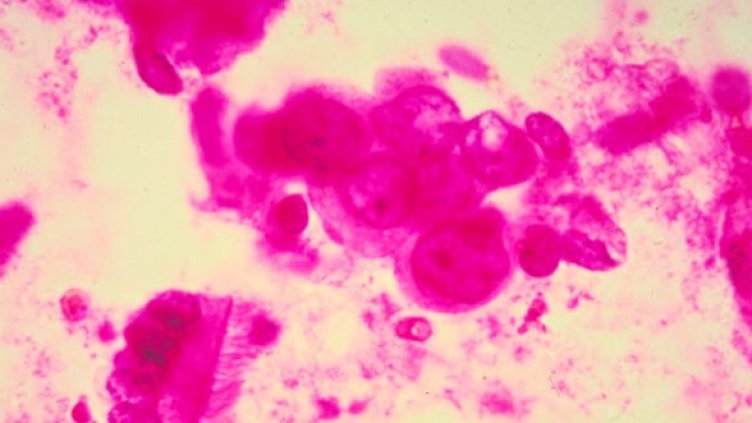

Изследователи от Канада са открили механизъм, с който може да се обясни как раковите клетки проявяват устойчивост към прилаганите терапии, съобщи "Дейли експрес".

Авторите на проучването от университета на Западно Онтарио са установили как биохимичните пътеки могат да бъдат "свързани наново" в раковите клетки. Това им позволява да пренебрегват сигналите, които обикновено предизвикват клетъчна смърт.

Целта на специалистите е била да разберат как раковите клетки придобиват селективно предимство за оцеляване, което им дава възможност да избегнат апоптозата - предизвиканата клетъчна смърт. Процесът е необходим за нормалната реорганизация на клетките.

Откритието дава надежда на учените за разработването на терапии, които да пречат на формирането на нови връзки или да ги неутрализират, за да могат раковите клетки да реагират на прилаганото лечение.